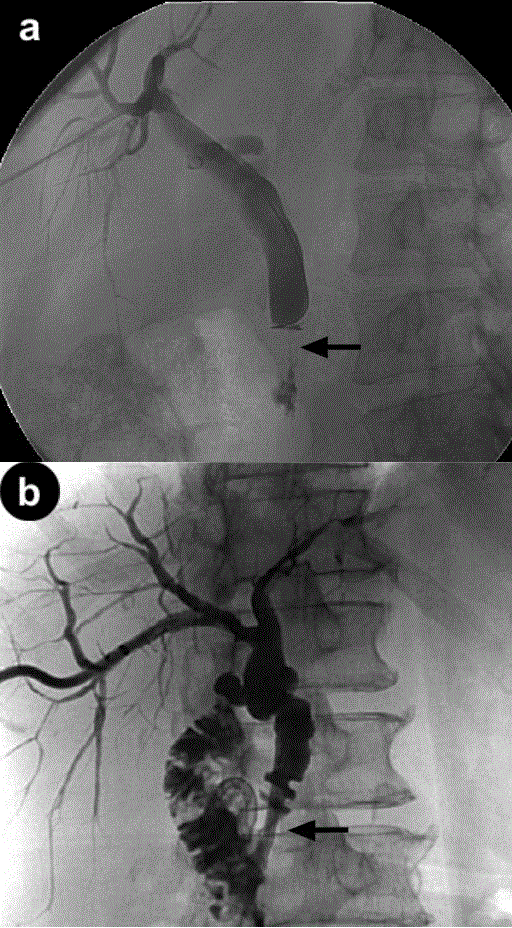

Figure 1. a. A distal stricture with shouldering (arrow) seen on percutaneous transhepatic cholangiography, highly suggestive of malignancy. b. Similar distal stricture (arrow) in another patient following percutaneous transhepatic stenting.